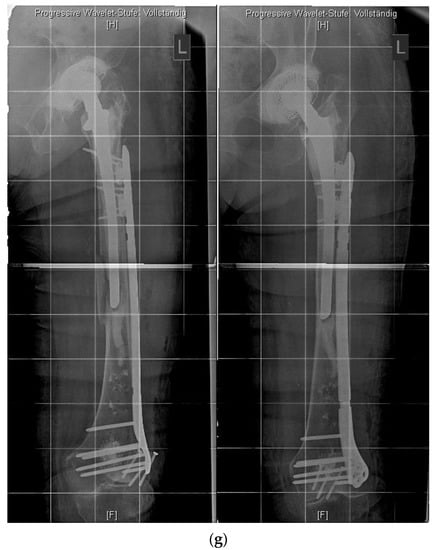

Hence, a special concept improving the bicortical screw fixation around intramedullary devices called the LOQTEQ® VA Periprosthetic Plate or ‘periprosthetic hinge plate’ was established by the company, aap Implantate AG. Multiple insertable hinges create the possibility to place the screws bicortically and alongside the enclosed stem. The square of the two polyaxial locking screws of the hinge constitutes 15 degrees to each direction. Since a central screw can be attached separately, further angle stabilization of the hinges can be achieved. The hinge is not attached to a plate hole, which could be staffed additionally with monocortical screws or cable cerclages in the diaphysis (Figure 3).

Figure 3.

(a) LOQTEQ VA Periprosthetic Plate (with kind permission of aap Implantate AG, Berlin, Germany). (b) Insertable hinge with each of the two variable angle screw options (with kind permission of aap Implantate AG, Berlin, Germany). (c) Periprosthetic fracture around a cemented stable total hip revision arthroplasty. (d) LOQTEQ VA Periprosthetic Plate with mounted aiming device. (e) LOQTEQ VA Periprosthetic Plate with four inserted hinges. (f) Variable angle screw placement around the hip revision stem. (g) Postoperative X-rays. Four hinges with each of the two variable angle screw options were used to fix the plate around the hip stem.

A biomechanical study investigated the characteristics of the LOQTEQ® VA Periprosthetic Plate in comparison with the standard locking compression plate with locking attachment plate, for the treatment of periprosthetic fractures in a Vancouver B1 fracture model.

The LOQTEQ® VA Periprosthetic Plate showed superior biomechanical results (axial stiffness and cycles to failure) compared to the standard locking compression plate in combination with the locking attachment plate [21].